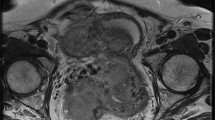

Fibromas, thecomas and fibrothecomas are classified as sex cord-stromal tumours and are the most common benign solid lesion of the ovaries. These tumours are usually asymptomatic and there may be an association with ascites and pleural effusion (Meig syndrome). Fibrothecomas consist of both fibrous tissue and theca cells with lipidic content. They present as a well-circumscribed solid mass with low to intermediate signal intensity on T1-weighted and low signal intensity on T2-weighted images, although there may be some scattered areas of cystic degeneration with high signal intensity on T2-weighted scans (Fig. 16). In fibromas, the prominent fibrosis with abundant collagen content is responsible for the low signal intensity (Fig. 17), while in thecomas, the mainly lipidic content of theca cells may be depicted at chemical-shift imaging [7]. After contrast administration, only a minimal enhancement can be demonstrated. Differential diagnosis of fibrothecomas includes pedunculated uterine leiomyomas; however, the multiplanar imaging along with the absence of the normal ipsilateral ovary are useful in distinguishing them.

Fibrothecoma in a 66-year-old woman. (a) Axial and (b) sagittal T2-weighted images show a heterogeneous solid mass (white arrows) with low to intermediate signal intensity. Some areas of cystic degeneration with high signal intensity can be seen within the lesion (white arrowheads). (c) Axial T1-weighted image confirms the solid appearance of the lesion (white arrow). (d) Photomicrograph (H&E X200) shows fascicles of spindle cells with centrally placed nuclei and a moderate amount of pale cytoplasm

Fibroma in a 44-year-old woman. (a) Axial, (b) coronal and (c) sagittal T2-weighted images show a polilobulated solid mass (white arrows) with homogeneous low signal intensity. (d) Axial and (e) coronal contrast-enhanced fat-suppressed T1-weighted images show the homogeneous enhancement of the lesion (white arrows). (f) Photomicrograph (H&E X20) shows closely packed spindle stromal cells arranged in storiform pattern with hyaline bands